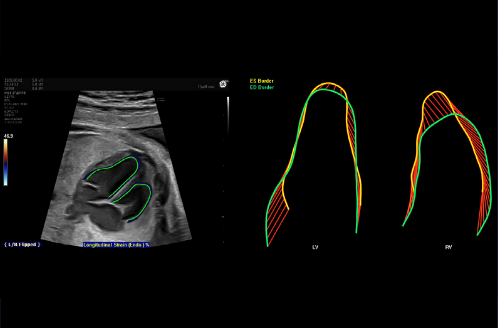

Esempio di analisi speckle tracking che dimostra la contrattilità del cuore. I bordi dell’endocardio sono tracciati a sinistra e la deformazione di entrambi i ventricoli è rappresentata a destra. Successivamente il software fornisce valutazioni oggettive dei parametri della funzionalità cardiaca.

Rappresentazione grafica della deformazione dei ventricoli

L’ecocardiografia speckle tracking è un metodo avanzato, non invasivo, e di rapida, ma accurata acquisizione di immagine, basato sull’interazione dell’onda ultrasonora con i tessuti cardiaci fetali, che emette dei marker acustici chiamati “speckles” (macchioline). Questi ultimi si spostano durante l’intero ciclo cardiaco seguendo la dinamicità del miocardio nelle fasi di riempimento ed eiezione. Il processo di acquisizione dei parametri avviene in maniera offline su brevi clip in 2D. Tramite software dedicati (Feta Heart Quantification) e attraverso un processo semiautomatico è possibile analizzare quantitativamente la funzione globale e regionale del miocardio ventricolare ed atriale. Valutando lo spostamento degli speckle che formano l’immagine ecocardiografica bidimensionale durante un intero ciclo cardiaco, è possibile ottenere la misurazione di vari parametri di deformazione miocardica, consentendo così una valutazione oggettiva e quantitativa dell’allungamento, dell’accorciamento e della rotazione miocardica.